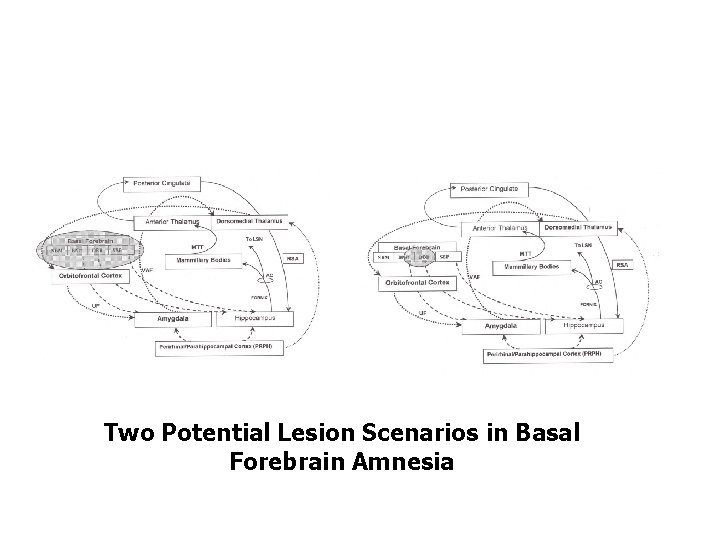

Two Potential Lesion Scenarios in Basal Forebrain Amnesia